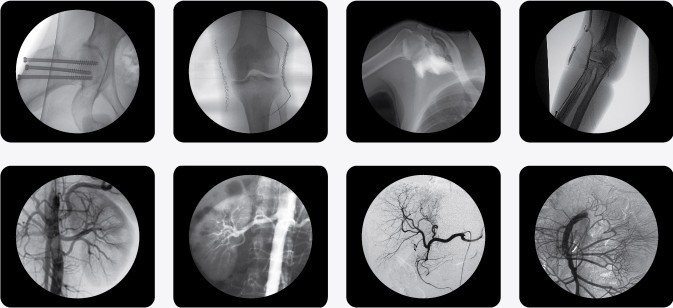

廣泛應(yīng)用于 介入科、骨科、外科、矯形外科、泌尿外科、脊柱外科、腹部外科、疼痛科、心臟科、消化科、婦科及手術(shù)室等。

三、C型臂X光機(jī)PLX7000B數(shù)字高清影像,支持您做出精確診斷

·全數(shù)字化百萬像素影像采集系統(tǒng),優(yōu)化設(shè)計(jì)和配置,為您提供高分辨率、高灰階圖像,支持您做出精確診斷。

·專業(yè)的圖像處理系統(tǒng),具備非凡處理能力,確保您的所想即您的所得

1、內(nèi)置先進(jìn)圖像自動(dòng)優(yōu)化處理、增強(qiáng)模塊,實(shí)時(shí)顯示自動(dòng)優(yōu)化后的清晰臨床影像。

2、專業(yè)的影像處理工作站具備窗寬窗位調(diào)節(jié)、自動(dòng)伽瑪校正、興趣點(diǎn)、反相、降噪、平滑、銳化等豐富且強(qiáng)大影像處理功能,帶給您更強(qiáng)大的診斷信心。

·專用高清醫(yī)用液晶顯示系統(tǒng),呈獻(xiàn)給您高亮度、高對(duì)比度的臨床圖像;對(duì)比自然,有益于診斷的圖像細(xì)節(jié)顯示更加清晰、層次更加豐富